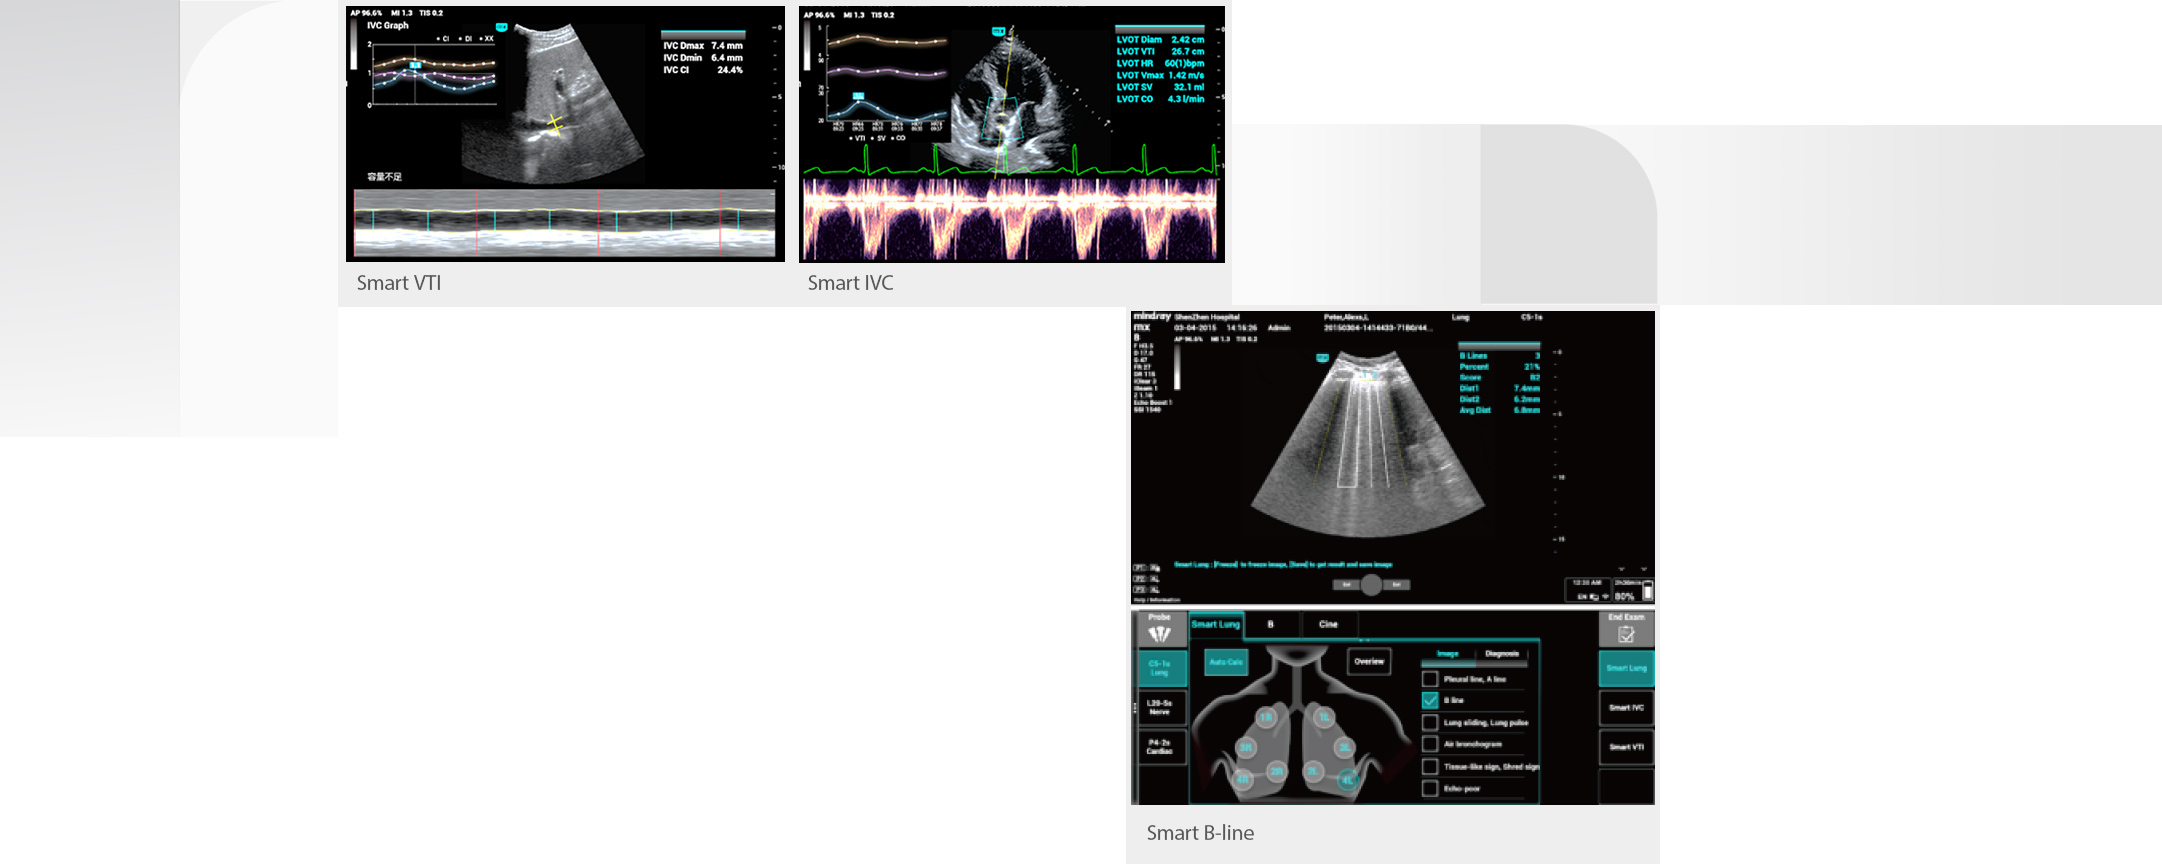

Por lo tanto, la monitorizaciÃģn estrecha de los fluidos de los pacientes y la gestiÃģn precisa de su volumen son de suma importancia. Sin embargo, la ecografÃa tiene la ventaja de ser mÃĄs intuitiva en la evaluaciÃģn dinÃĄmica de la funciÃģn cardiopulmonar y la hemodinÃĄmica de los pacientes y puede ayudar a los profesionales de cuidado de la salud de la UCI a tomar decisiones de tratamiento oportunas y observar los efectos del tratamiento en tiempo real.

Por lo tanto, la monitorizaciÃģn estrecha de los fluidos de los pacientes y la gestiÃģn precisa de su volumen son de suma importancia. Sin embargo, la ecografÃa tiene la ventaja de ser mÃĄs intuitiva en la evaluaciÃģn dinÃĄmica de la funciÃģn cardiopulmonar y la hemodinÃĄmica de los pacientes y puede ayudar a los profesionales de cuidado de la salud de la UCI a tomar decisiones de tratamiento oportunas y observar los efectos del tratamiento en tiempo real.